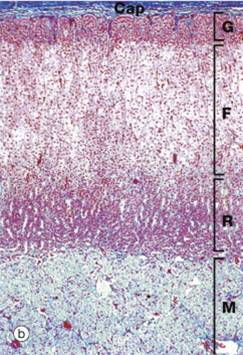

Identify the portions of this tissue. What is this gland?

Adrenal Gland

Cap: Capsule

C: Cortex

M: Medulla

Identify the layers of the Adrenal gland shown.

•Capsule (Cap)

•Cortex

–Three zones:

•Zona glomerulosa (G)

•Zona fasciculata (F)

•Zona reticularis (R)

•Medulla (M)